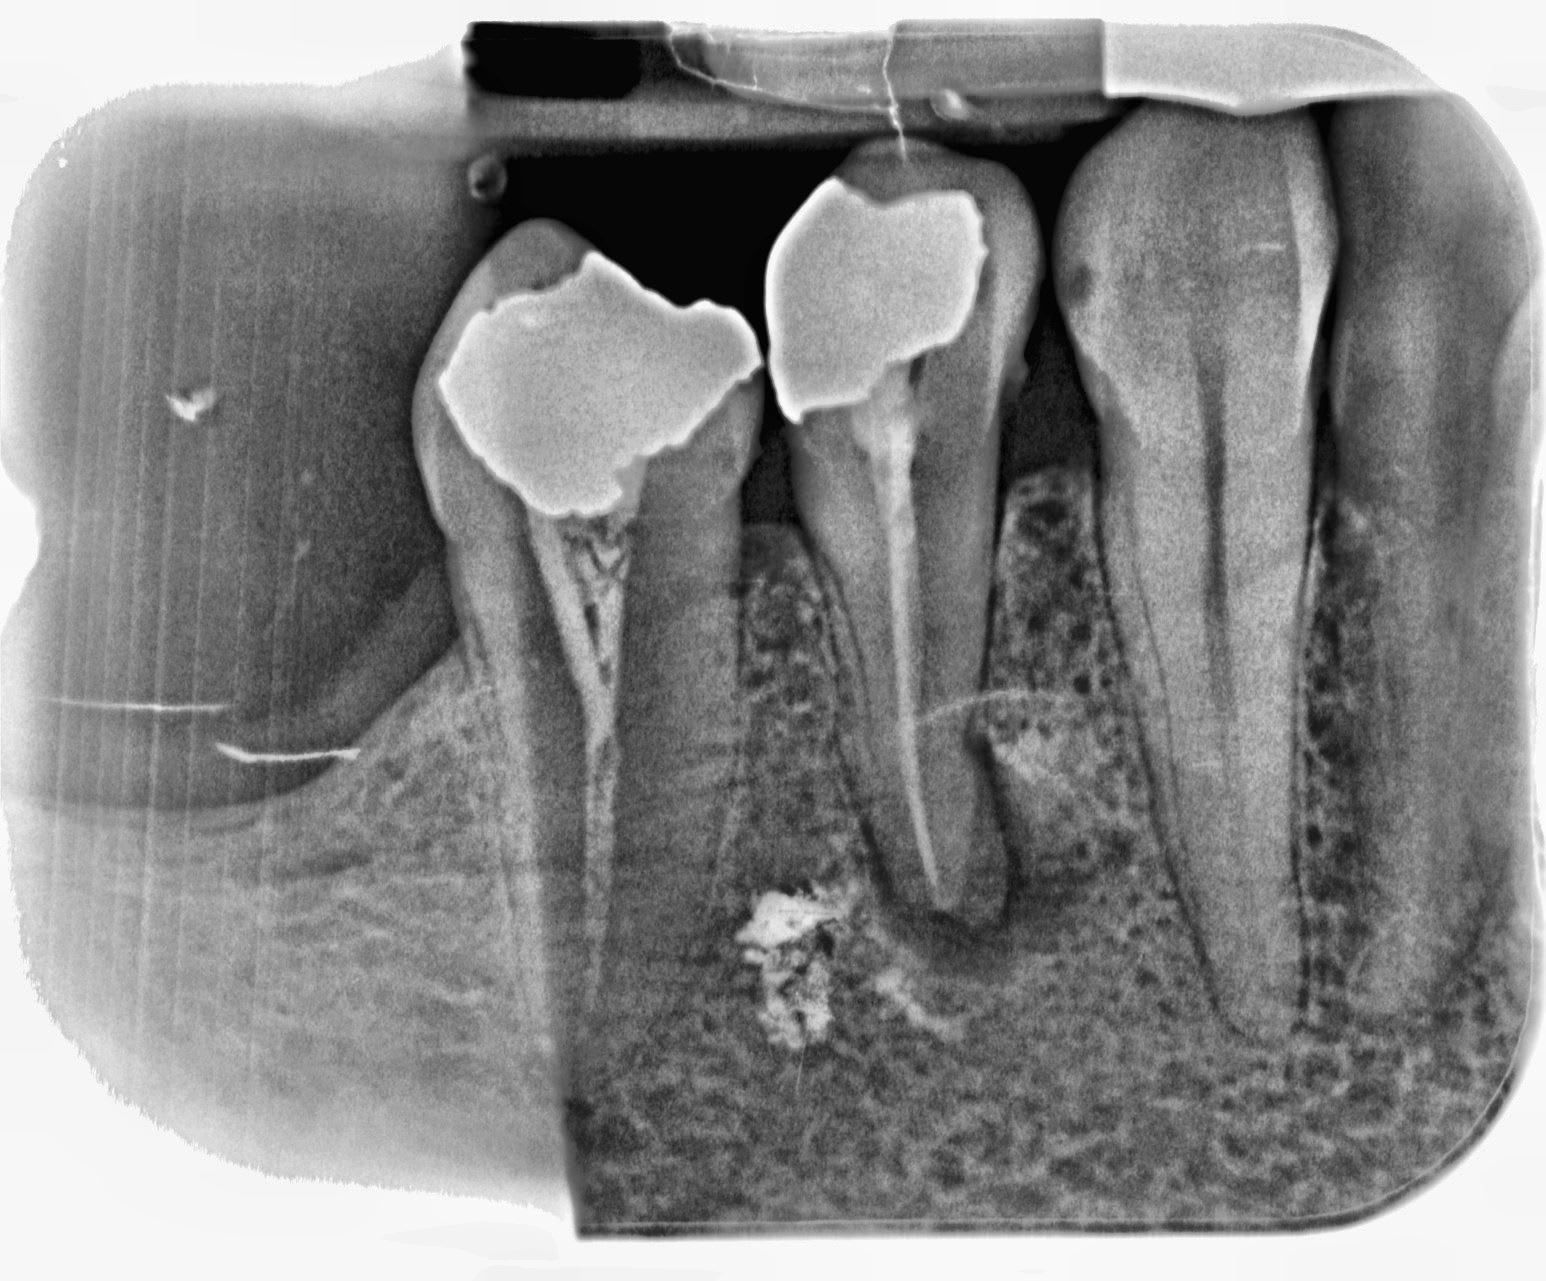

J'ai bloqué un openeur dans un canal ... du coup, j'ai inversé le sens de rotation de mon contre angle pour le débloquer. Et j'ai oublié de le mettre dans le bon sens au moment de thermo compacter.

Le cas était amusant, le confrère qui avait obturé n'avait pas trouvé le canal lingual.

Ça pue quand même un peu ton truc là… ton instrument traverse du tissus infectieux, le cône d’à côté dépasse lui aussi… et pour couronner le tout, la résection a cet endroit si ça foire c’est pas jojo. Ça sent le titane…

Sinon pour le compacteur pété, comme on dit, shit happens mais effectivement vu qu'il est sorti de la racine et qu'il baigne dans la LIPOE, m'est avis que c'est kaput.